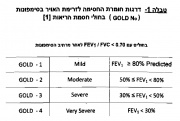

| 16:32, 7 במרץ 2015 | Gold table1.jpg (קובץ) |  |

373 קילו־בייטים | Motyk | 1 | |